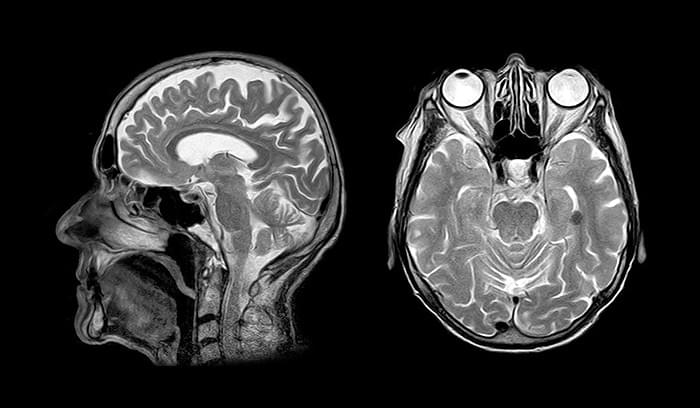

Due to their immunosuppressive properties, systemic glucocorticoids are estimated to be used by 0.5% to 3% of the population annually. Glucocorticoids are effective, but their use comes with some significant musculoskeletal and cardiovascular side effects. A recent BMJ Open study conducted a cross-sectional analysis to test the hypothesis that the usage of systemic and inhaled glucocorticoids was associated with alterations in grey matter volume (GMV) and white matter microstructure. Study: Association between use of systemic and inhaled glucocorticoids and changes in brain volume and white matter microstructure: a cross-sectional study using data from the UK Biobank. Image Credit: Atthapon Raksthaput / ShutterstockStudy: Association between use of systemic and inhaled glucocorticoids and changes in brain volume and white matter microstructure: a cross-sectional study using data from the UK Biobank. Image Credit: Atthapon Raksthaput / Shutterstock Background Related Stories Understanding how microglia change their states to adapt to different areas of the brain EEG tests reveal fentanyl's effects on the brain Tight control of blood sugar in teens may help reduce diabetes-related brain damage In addition to the physical side-effects mentioned above, the use of synthetic glucocorticoids could lead to neuropsychiatric symptoms, such as depression, mania, and even a significantly increased suicide (attempt) rate. In prior studies, overexposure to glucocorticoids has been shown to have adverse effects on the brain. Some studies have documented the reduction of the volume of specific regions in the brain, including the amygdala and hippocampus, in patients on a high dosage of synthetic systemic glucocorticoids. In patients with Cushing disease, long-term glucocorticoid excess is associated with cerebral atrophy and decreased cortical thickness. In such patients, reductions in white matter integrity throughout the brain have also been reported. A diffusion tensor imaging (DTI) analysis demonstrated globally reduced fractional anisotropy (FA), a microstructural architecture marker. The majority of studies on the effects of glucocorticoid overexposure have been conducted on small, selected populations. However, it remains to be seen whether these findings hold true in a broader sample of people using glucocorticoids, including inhaled glucocorticoids. About the Study Using data from the UK Biobank, a large population-based cohort study was conducted to address the above research gap. The hypothesis was that differences in white matter microstructure and brain volume could be identified between non-users and inhaled or systemic glucocorticoid users. For the study, adults were recruited between 2006 and 2010, and the exclusion conditions centered around endocrinological, psychiatric, or neurological history and the use of psychotropic drugs. The study included 557 inhaled glucocorticoid users, 222 systemic glucocorticoid users, and 24,106 controls. As well as assessing cognitive outcomes, the study evaluated differences in emotional well-being and cognitive function. Researchers hypothesized that the use of glucocorticoids would result in reduced gray matter volumes in the limbic system and hippocampus, decreased fractional anisotropy (FA), and increased mean diffusivity (MD) throughout the brain, as well as poorer cognitive and emotional functions. Key Findings It was observed that systemic and inhaled glucocorticoids were associated with changes in several brain imaging parameters. In addition, glucocorticoid effects on white matter microstructure, which were reported in previous studies, were also detected in the present study. Inhaled and systemic glucocorticoid use was found to be related to reduced white matter integrity. In other words, a lower FA and higher mean diffusivity (MD) were observed compared with controls. Based on this observation and the fact that a large sample size was considered, it could be concluded that the adverse effects of glucocorticoids were quite widespread. Chronic glucocorticoid use showed a duration-dependent or dose-dependent effect on white matter microstructure. The most significant effects were observed in chronic systemic glucocorticoid users, somewhat significant effects were observed in systemic glucocorticoid users, and the smallest effects were observed in the case of inhaled glucocorticoid users. The findings are important because synthetic glucocorticoids have common neuropsychiatric side effects, and they may aid in treating patients who report them.